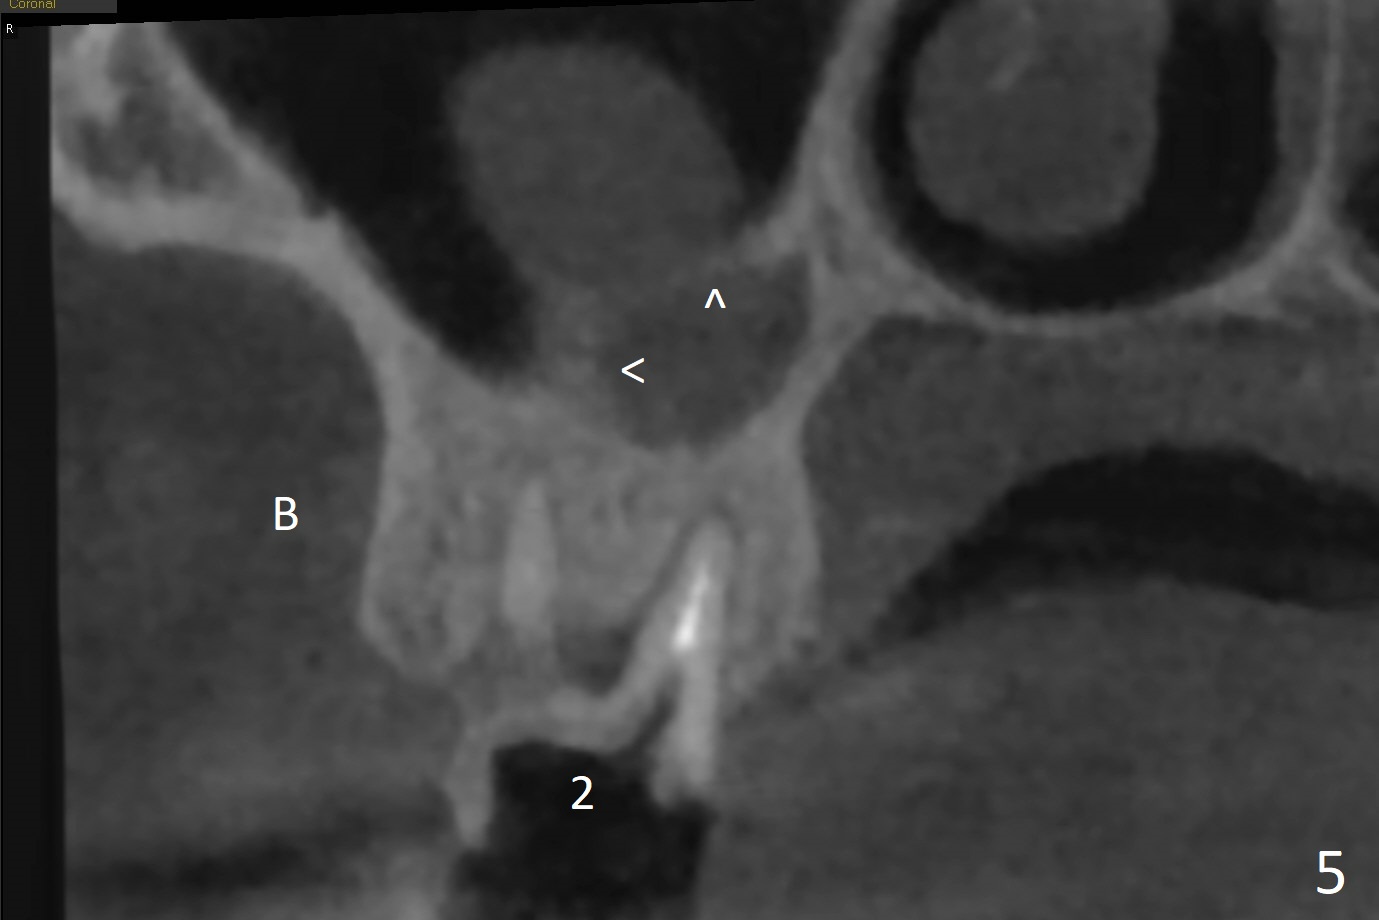

A 51-year-old man agrees to have #2 residual root to be extracted for implant. Panoramic X-ray (Fig.1) and CT coronal section (Fig.2) show maxillary sinus mucocele (*). A 5x10 mm implant will be placed not to intrude into the sinus (Fig.2,3). In case sinus membrane perforation, prepare PRF membranes for repair. The apex of the implant will be engaged to an apparent sinus septum for stability (Fig.4,5,7 arrowheads). Fig.4,5,6 are sagittal and coronal sections and 3-D image of Fig.3 without an implant at #2, while Fig.7 is the inferior view of Fig.6 (arrow).